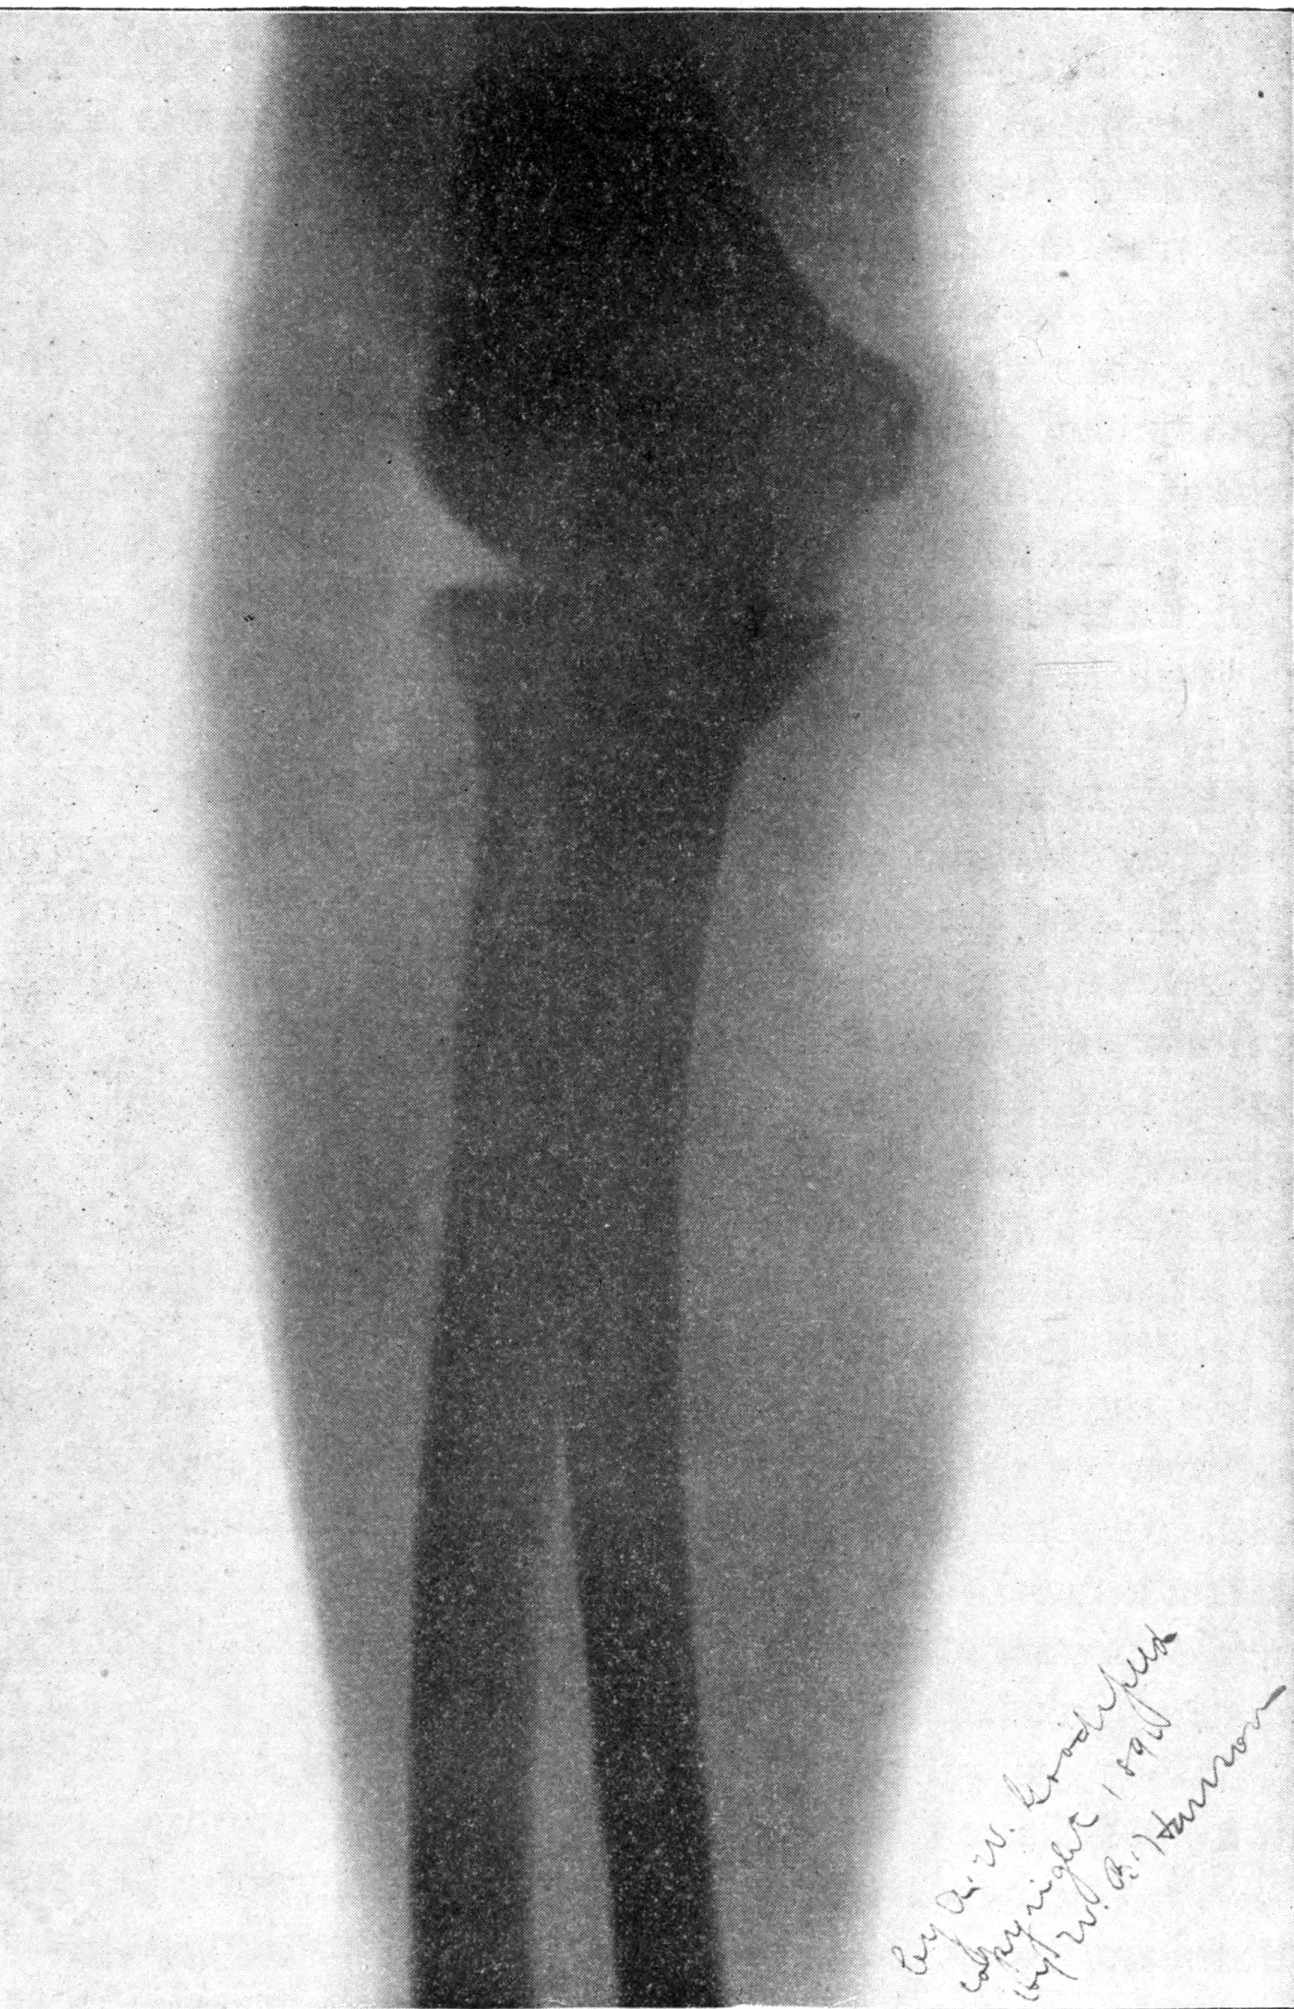

Fig. 1.—Head.

Fig. 2.—Broken Arm, Overlapping.

(Due to defective setting.)

Fig. 3.—Ribs.

Fig. 4.—Knee, Knickerbocker Buttons, Bullet in Femur.

FROM SCIAGRAPHS BY PROF. DAYTON C. MILLER. § 204.